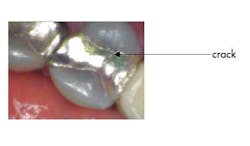

Mrs. Jones comes in for her routine six-month checkup and presents with not much out of the ordinary — chief complaint: none. Head/neck oral cancer screening: normal. Periodontal probing: normal. Radiographs: normal. Hard tissue exam: normal, EXCEPT on tooth No. 13 you notice that the existing MOD amalgam has a recent small fracture on it that, in the long run, will more than likely cause her problems (you know this crack is recent because you referenced her new-patient exam photos). What do you say to her? Mrs. Jones, you have a large filling on your upper left tooth that is breaking down …

Here’s what can be done. Take a clinical photo from multiple views, sit her up in the chair, and say: “Mrs. Jones, this is your upper left tooth. See this fracture line? It is new since your last visit. Here are your options. We can put a filling in it, but it would be even bigger than this one and the tooth could break. It could need a root canal on it, or it could fracture in a manner that would make it difficult to restore. We could also do a crown on it to hold it together and you likely will not need to address this tooth again in the future (pending good home care, etc.). Since there doesn’t appear to be a cavity on it, we can also clinically observe it for changes at your next visit, keeping in mind though that not all is visible to the naked eye.”